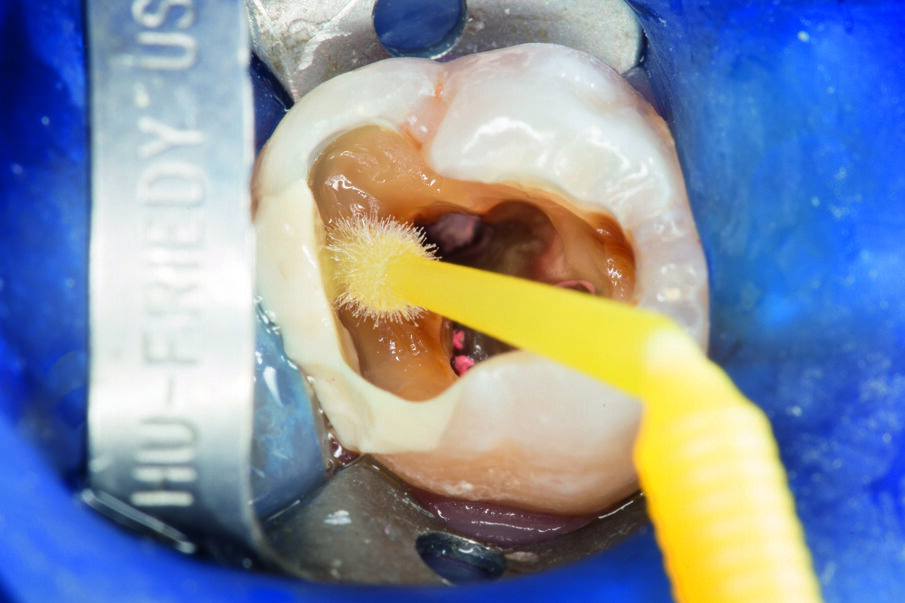

This case below shows a posterior tooth with an endodontic treatment followed by an indirect crown restoration. SDR® Plus is used as a core build up material before the crown was seated.

This case involves the use of SDR® Plus composite as a core build-up material. The outstanding flowability of SDR® Plus composite allows complete filling of the pulp cavity, even in the smallest recesses; the composite was placed in two stages to ensure thorough polymerisation. The periphery of the tooth was then prepared, preserving a layer of enamel at the preparation margin to ensure effective bonding of an all-ceramic crown. This was bonded with the Calibra® system. This protocol thus avoids iatrogenic mechanical strains on the tooth roots during core build-up. This treatment, involving a tooth/restoration monoblock with SDR® Plus composite and crown using only adhesive techniques, provides for outstanding biomechanical and aesthetic results.

Fig. 3: Application of the etch&rinse adhesive Prime&Bond Universal™

Fig. 4: First layer of SDR® Plus was placed at the cavity bottom. SDR® Plus self-levels within a few seconds and can be applied to 4mm.

Fig. 5: SDR® Plus first increment was light-cured for 20 sec, before a second layer of SDR® Plus was placed and light-cured.